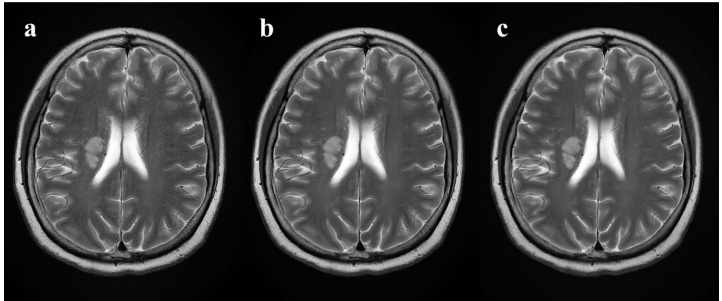

两位观察者对ACS-DLR序列的整体图像质量评分达5分,显著优于ACS序列的4分(P<0.001),与PI序列相当(P>0.05)。在伪影评估方面,三组序列在截断伪影、运动伪影、脑脊液流动伪影等方面均获满分,血管搏动伪影评分也显示ACS-DLR与PI无统计学差异。如图1所示,DLR技术有效消除了ACS原始图像的背景噪声,使图像质量媲美传统PI序列。